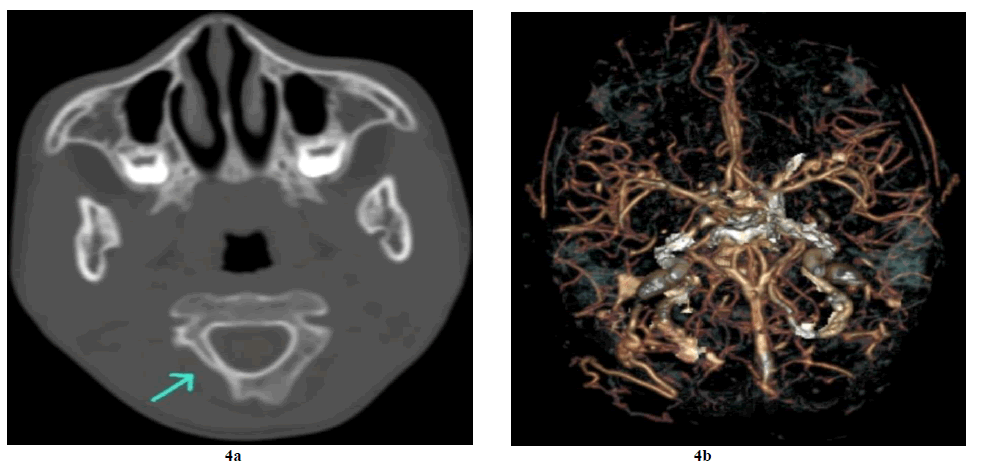

NECT shows a soft tissue attenuation mass lesion of size 7 x 2.2 cm x 1.3 cm in the occipital scalp region on the right side and is seen extending up to the nape of the neck, the ligament nuchae at the spinous process of C1/ C2. The above mass lesion is not showing any significant enhancement in contrast and no e/o intracranial extension on CECT. On the bone window, there is underlying bone erosion and a hypoplastic posterior arch of C1 on the right side (Figure 4a). Rt posterior occipital artery and venous plexus are prominent on CTA (Figure 4b and Figure 5).

Figure 5. Non-Contrast Computed Tomography (NCCT) of the head revealed a soft tissue density mass lesion involving the right occipital region extending posteromedially towards the spinous process of C1 through the inter & intramuscular planes of Rectus Capitus Post Major (RCPM), Obliqus Capitis Inferior(OCI), Semispinalis Capitis (SSC), Spenius Capitis (SC) and trapezius. There is a small bony defect in the right occipital bone